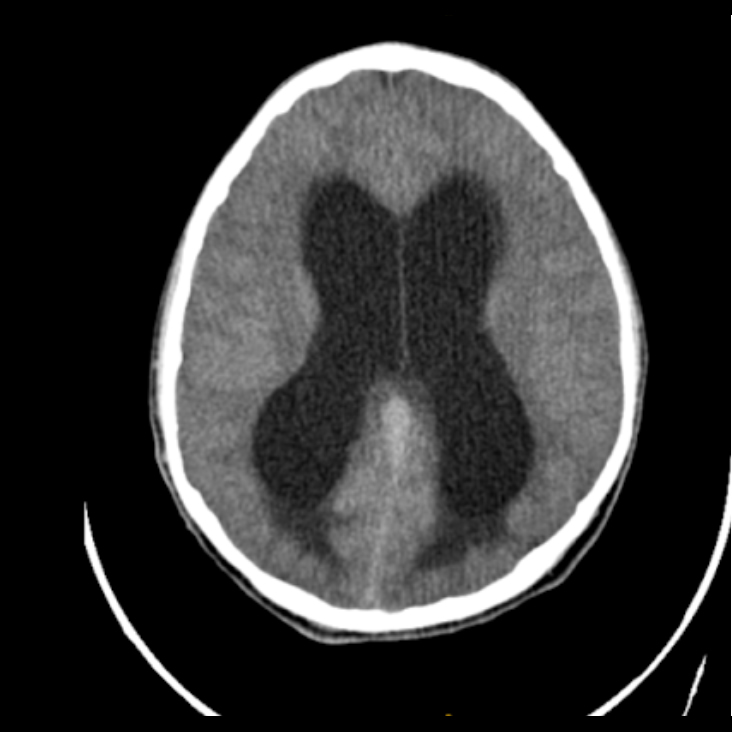

Abril 2022. Sanatorio Del Salvador Paciente de sexo masculino de 10 años de edad, consulta por cefalea